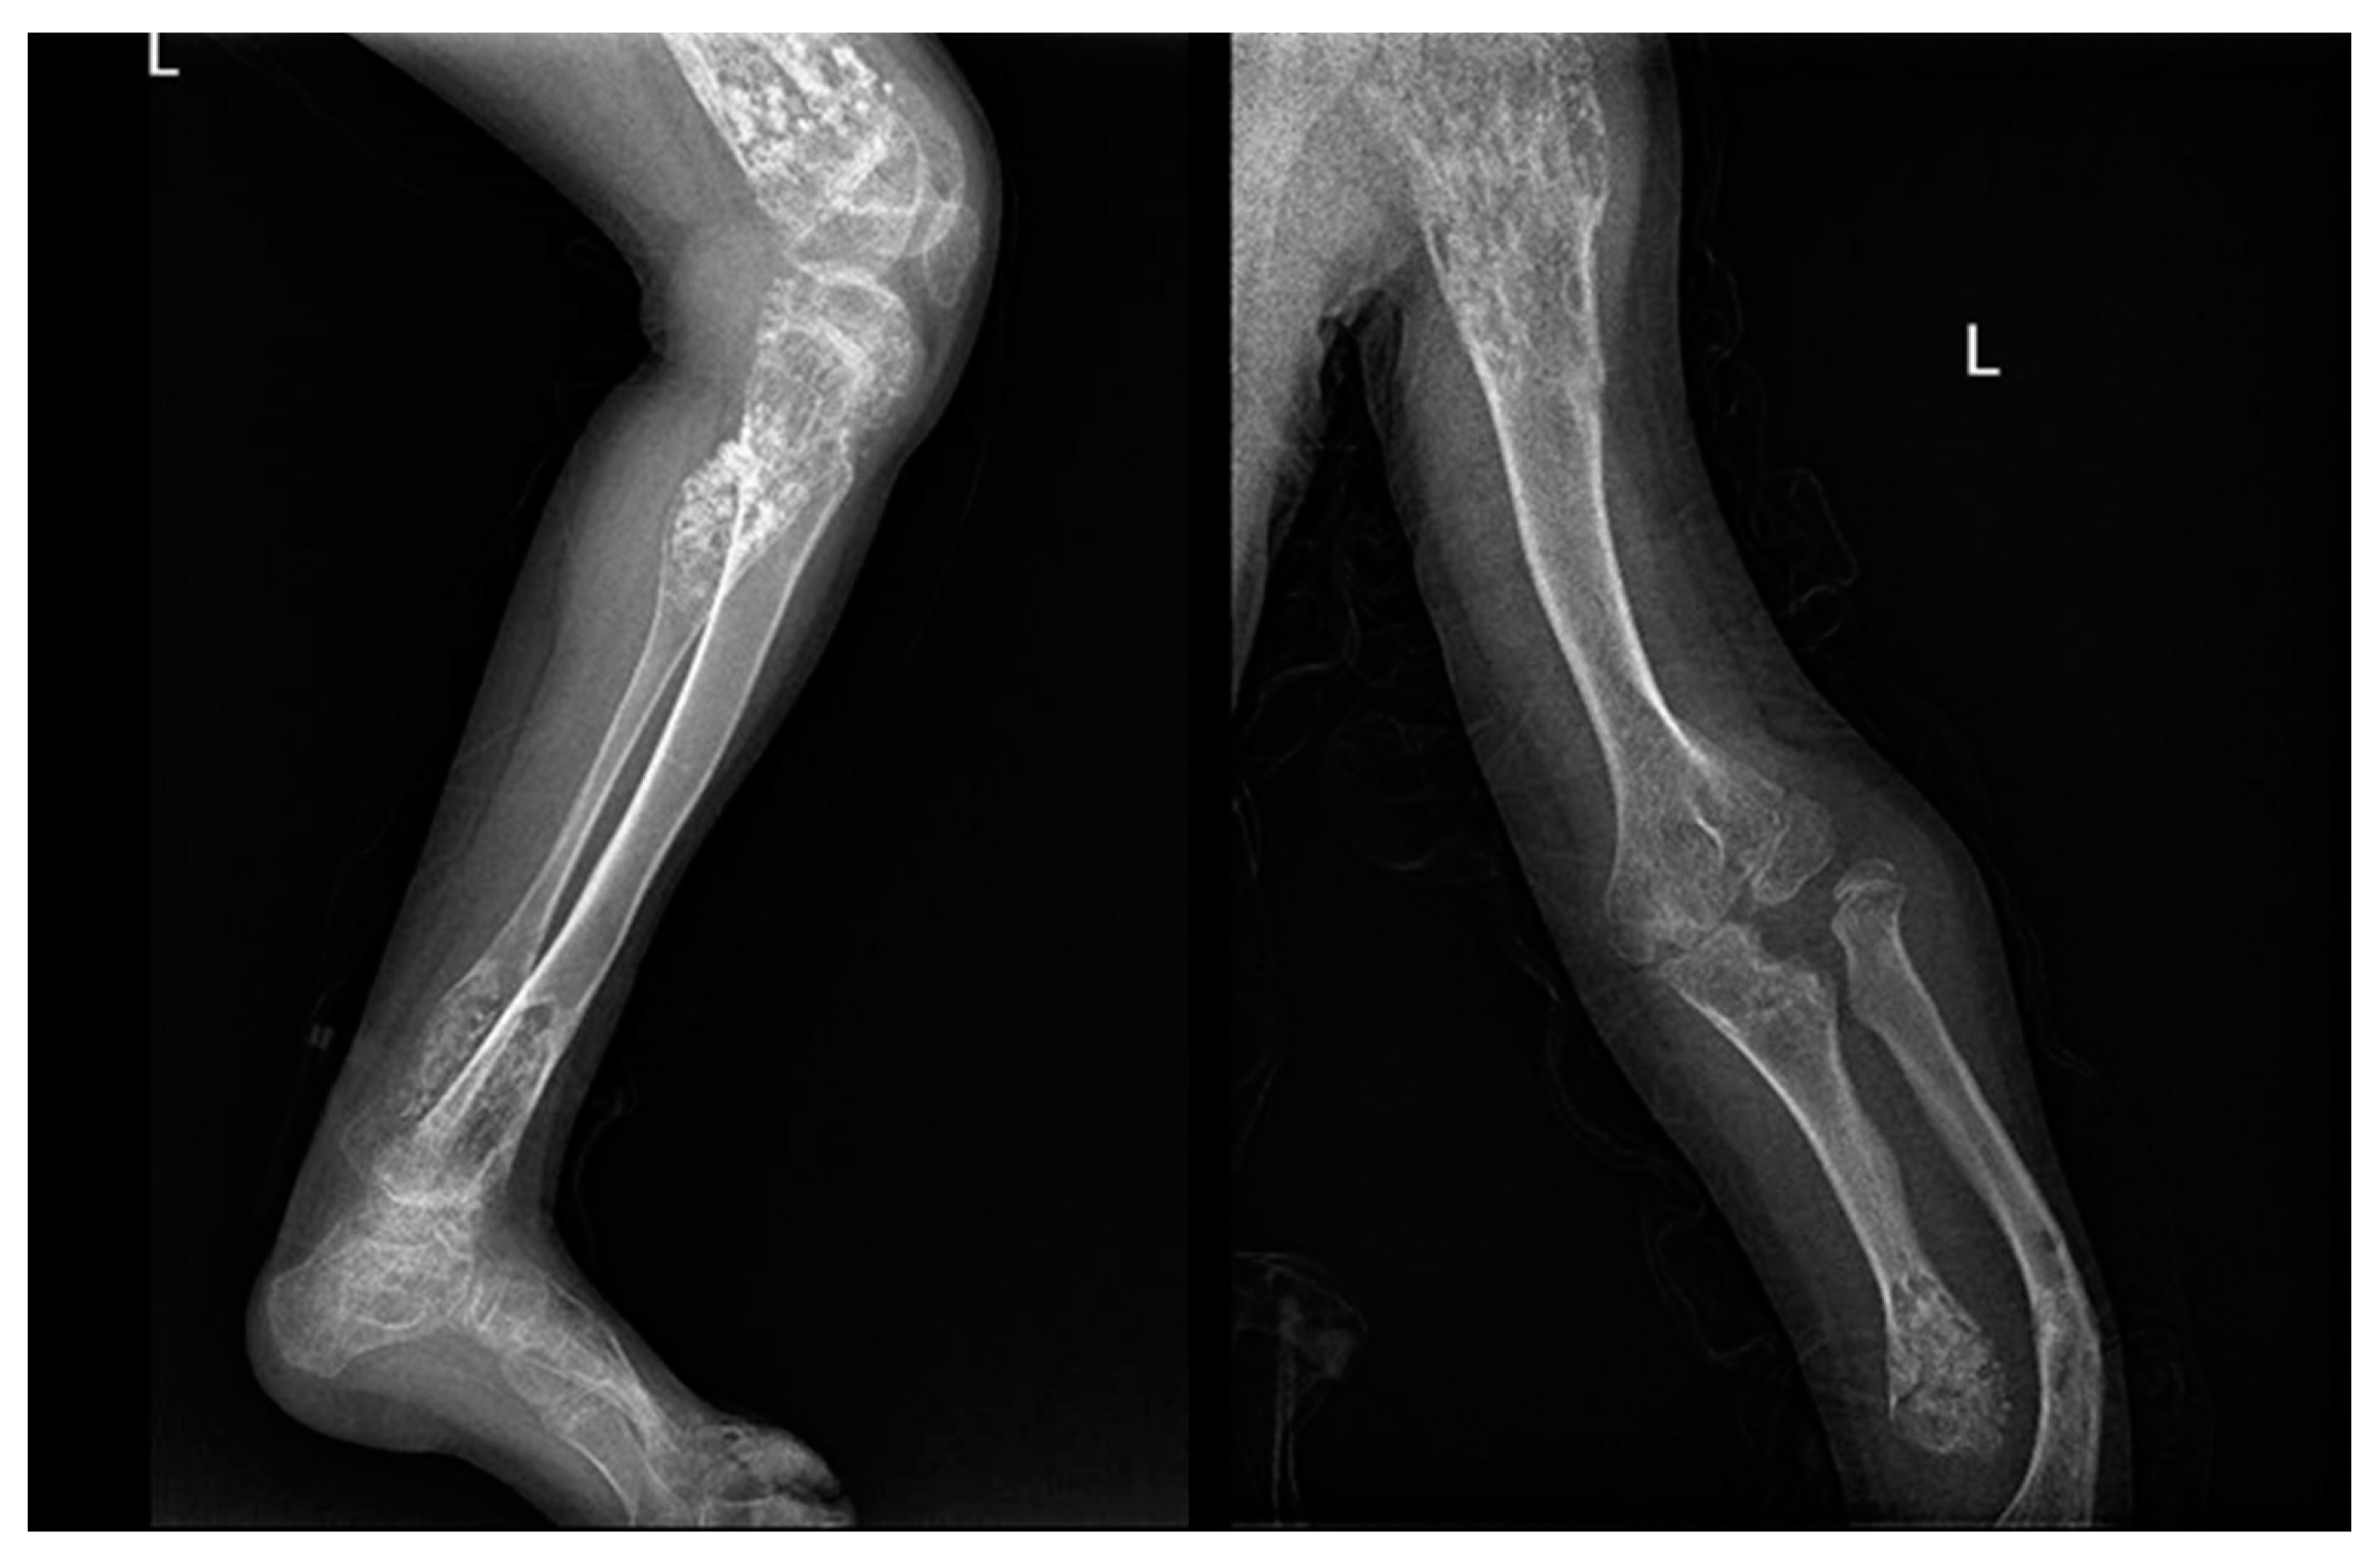

Figure 1. X-rays and CT scan of a tibial fracture that occurred in the development site of an Osteoid osteoma.

In X-ray examination, a bone-forming tumor appears as a nidus surrounded by sclerotic tissue. It may be hard to identify when it is intra-articular, therefore requiring further look examination. The second-level exam is a CT scan, which displays a small, defined nidus surrounded by a sclerotic reaction which may contain calcifications. Bone scintigraphy usually shows arterial phase uptake in the nidus due to its high vascular concentration and lower concentration in the reactive surrounding bone. There is a typical sign called the double-density sign which is diagnostic. It is fundamental to pay attention to growth plates since they can obscure the signal if the osteoid osteoma is in their proximity; therefore, it can be helpful to evaluate the contralateral side. Other imaging techniques may help the diagnostic workup, but those must be considered case by case [19,20,21] (Figure 1).